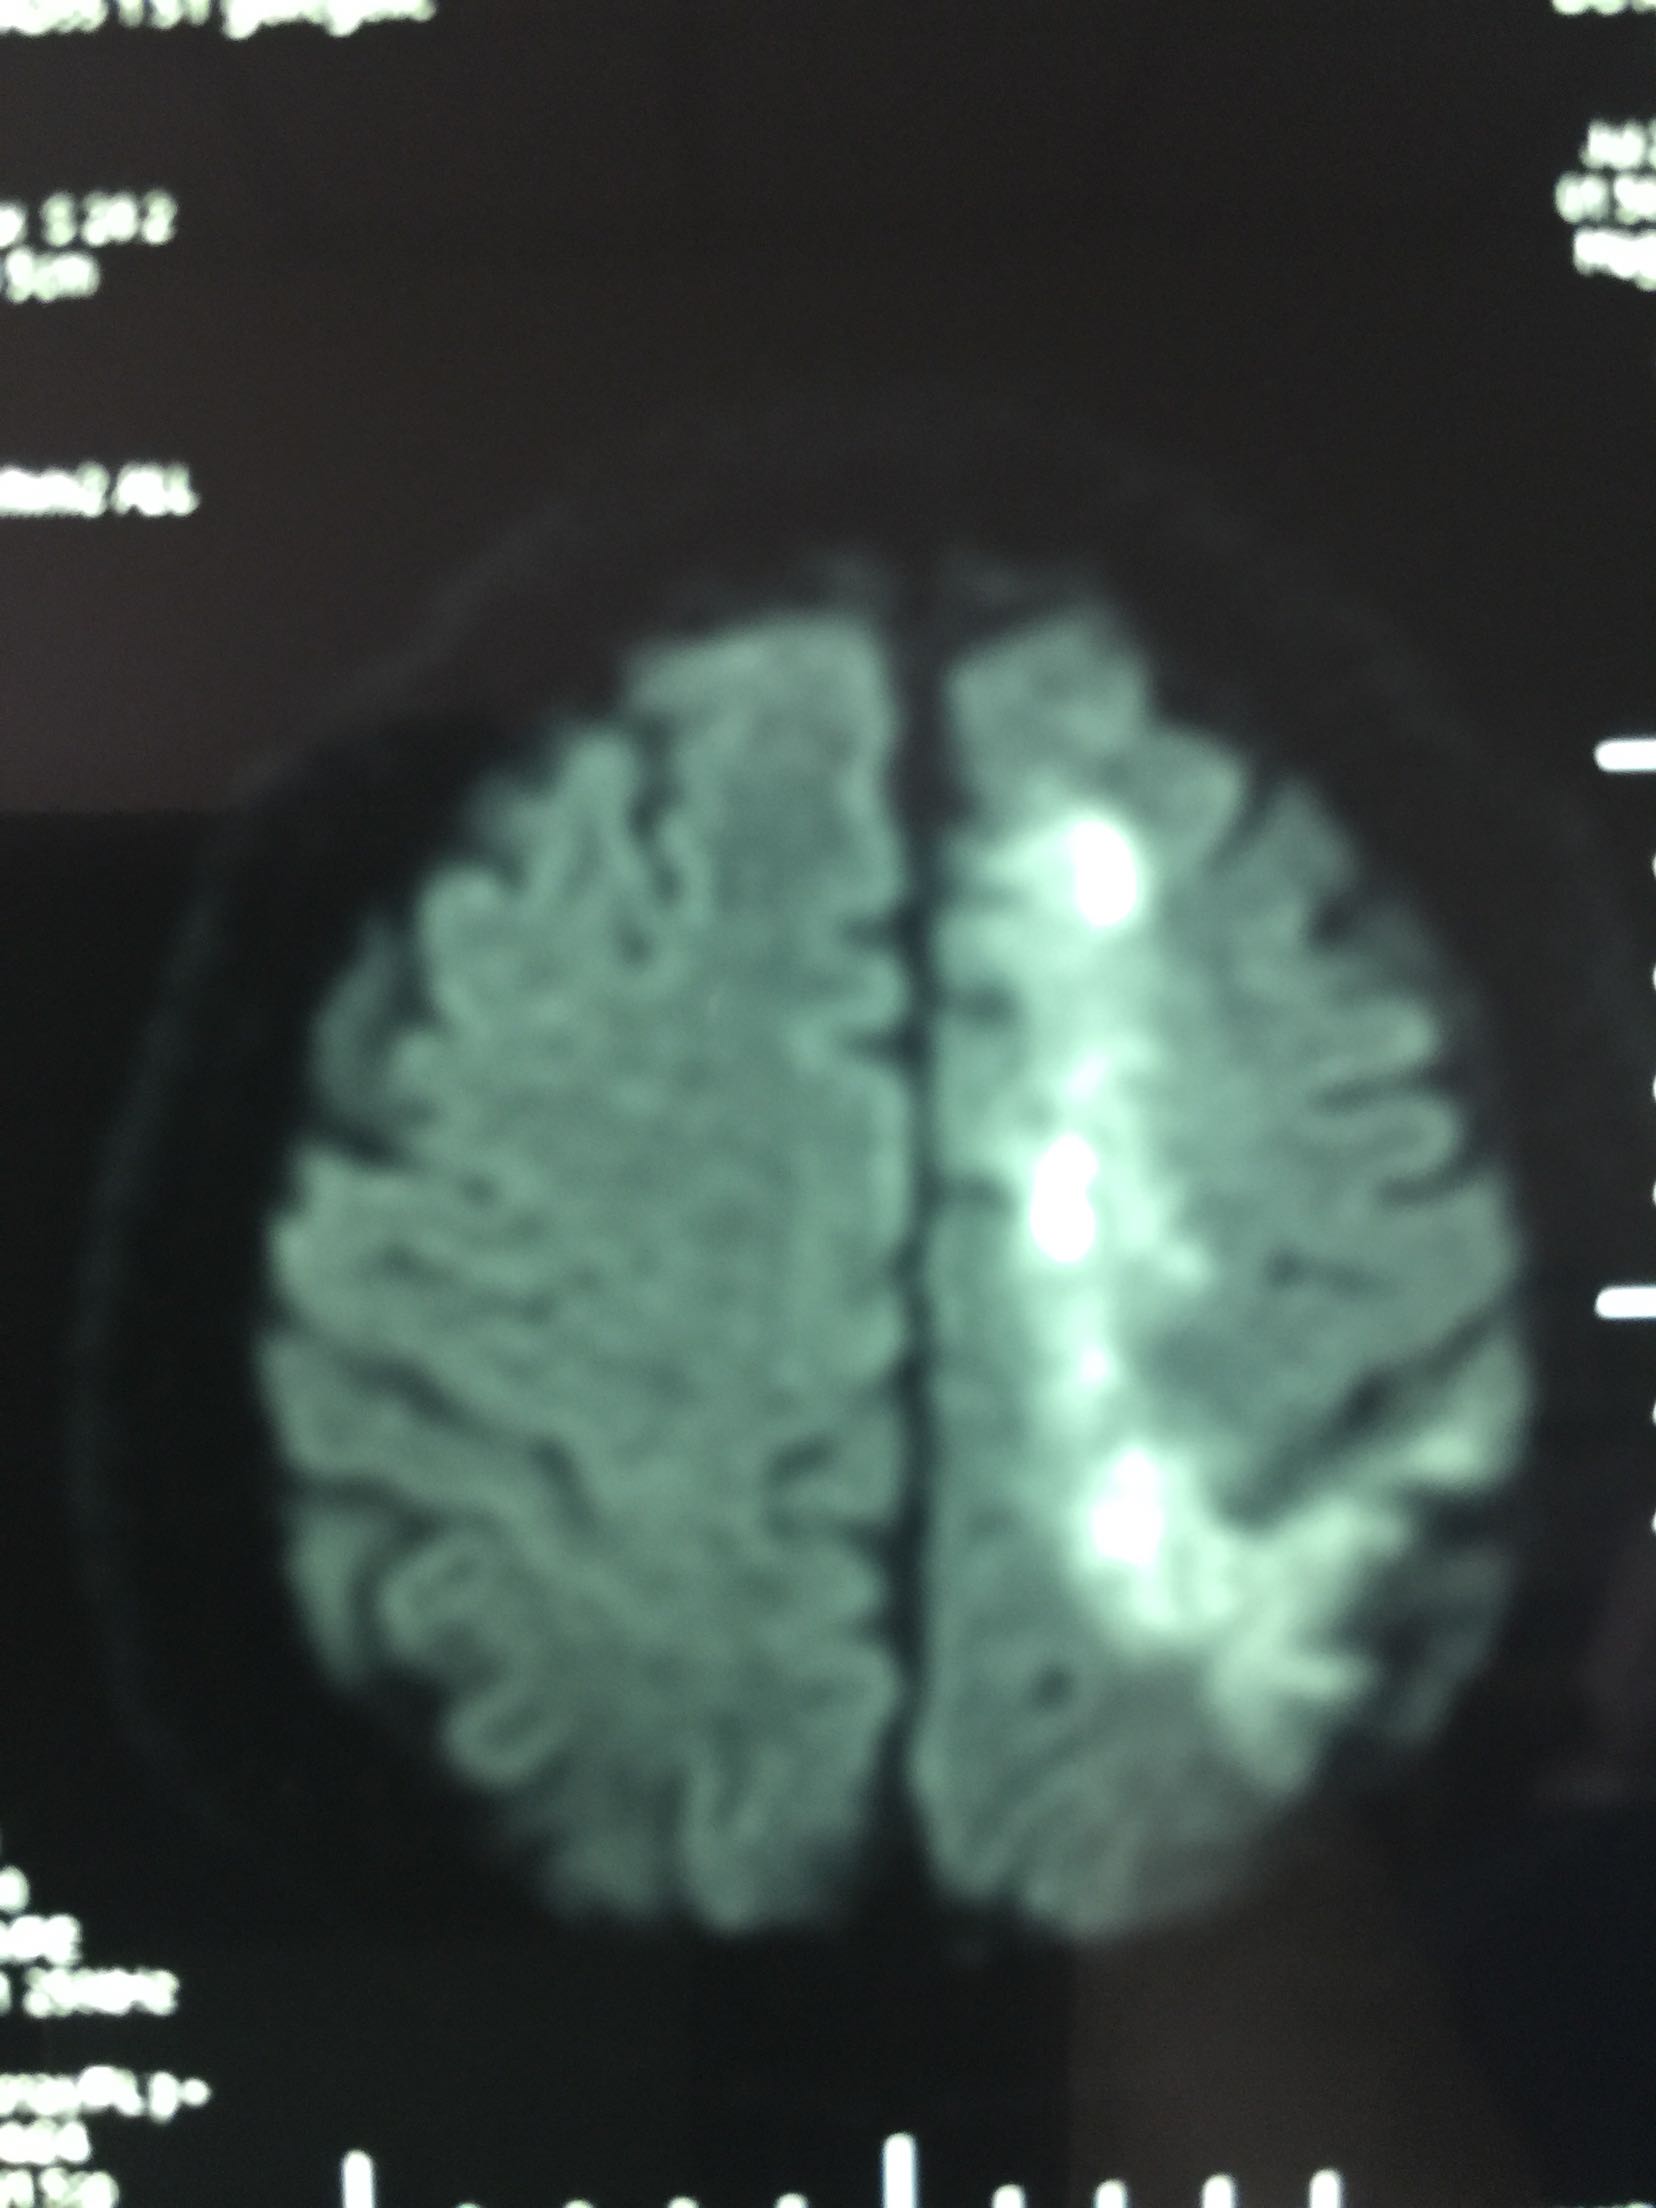

查体:T:36.5℃ P:68次/分 R:18次/分 Bp:120/70mmHg 内科系统:正常 神经系统:神志清楚,言语欠流利,查体合作,平车推人病房。左侧鼻唇沟浅,伸舌左偏,左侧肢体肌力0级,左侧肢体腱反射消失,左巴士征阳性。 辅助检查:血尿常规:正常 肝功、生化:正常 LDL-ch:5.12mmoL/l 心电图:窦性心律 头MRI+MRA、头CTA:

见下图

诊断:脑梗死 右侧大脑中动脉M1段重度狭窄 治疗:阿替普酶溶栓 醒脑静营养神经 长春西汀改善循环 丁苯肽建立侧枝循环 24小时后阿司匹林 氯比格雷抗血小板 瑞舒伐他汀降脂稳定斑块